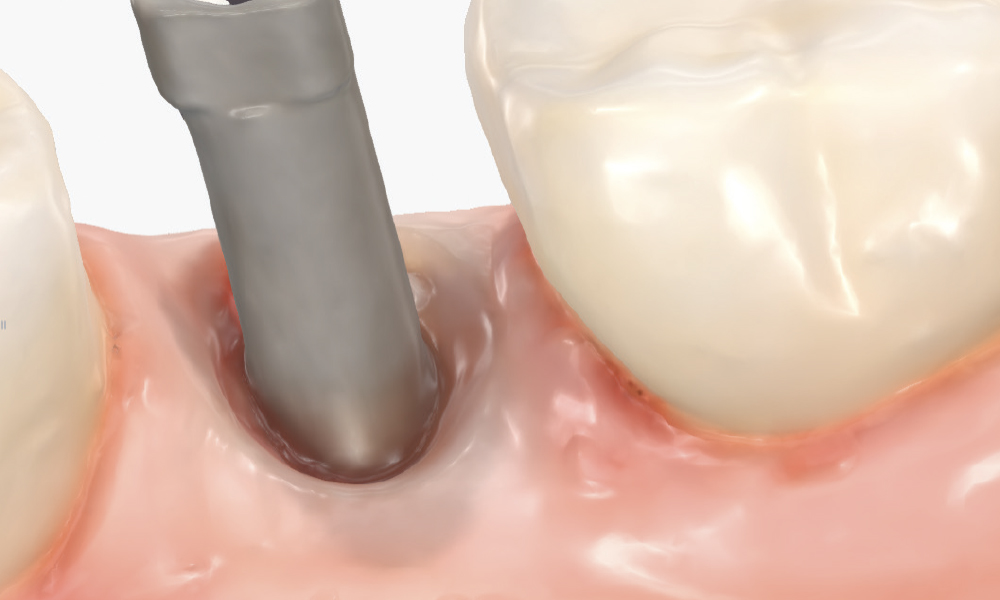

Thoroughly Scan the Scan Body Geometry

Thoroughly Scan the Scan Body Geometry. Complete, high-resolution capture of the scan body is non-negotiable. This is how laboratory software determines the precise three-dimensional position and angulation of the implant. The software matches the scanned scan body with its library file to establish the implant location in space. Scan from multiple angles to ensure all identifying features and surfaces are captured, as incomplete scan body data leads to misaligned restorations regardless of how perfect the rest of the scan appears. Verify that all reference markers, grooves, or geometric features are clearly visible in the acquired scan.

Implant post in socket